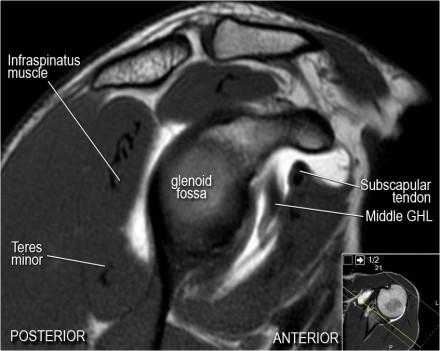

Изображение передних отделов плечевого сустава.

Нормальная анатомия плечевого сустава в аксиальных изображениях и контрольный список.

- поищите os acromiale, акромиальную кость (добавочная кость, расположенная у акромиона)

- обратите внимание что ход сухожилия надостной мышцы параллелен оси мышцы (это не всегда так)

- обратите внимание что ход сухожилия длинной головки двуглавой мышцы в области прикрепления направлен на 12 часов. Область прикрепления может быть различной ширины.

- обратите внимание на верхние отделы суставной губы и прикрепление верхней плече-лопаточной связки. На данном уровне ищется SLAP-повреждение (Superior Labrum Anterior to Posterior) и варианты строения в виде отверстия под сутавной губой (sublabral foramen - подгубное отверстие). На этом же уровне по задне-боковой поверхности головки плечевой кости визуализируются повреждение Хилл-Сакса.

- волокна сухожилия подлопаточной мышцы, создавая бицепитальную борозду, удерживают сухожилие длинной головки двуглавой мышцы. Изучите хрящи.

- уровень средней плече-лопаточной связки и передних отделов суставной губы. Поищите комплекс Буффорда. Изучите хрящи.

- вогнутость заднебокового края головки плечевой кости не следует путать с повреждением Хилл-Сакса, поскольку это нормальная форма для данного уровня. Повреждение Хилл-Сакса визуализируется только на уровне клювовидного отростка. В предних отделах мы сейчас на урвоне 3-6 часов. Здесь визуализируются повреждение Банкарта и его варианты.

- обратите внимание на волокна нижней плече-лопаточной связки. На данном уровне так же ищется повреждение Банкарта.